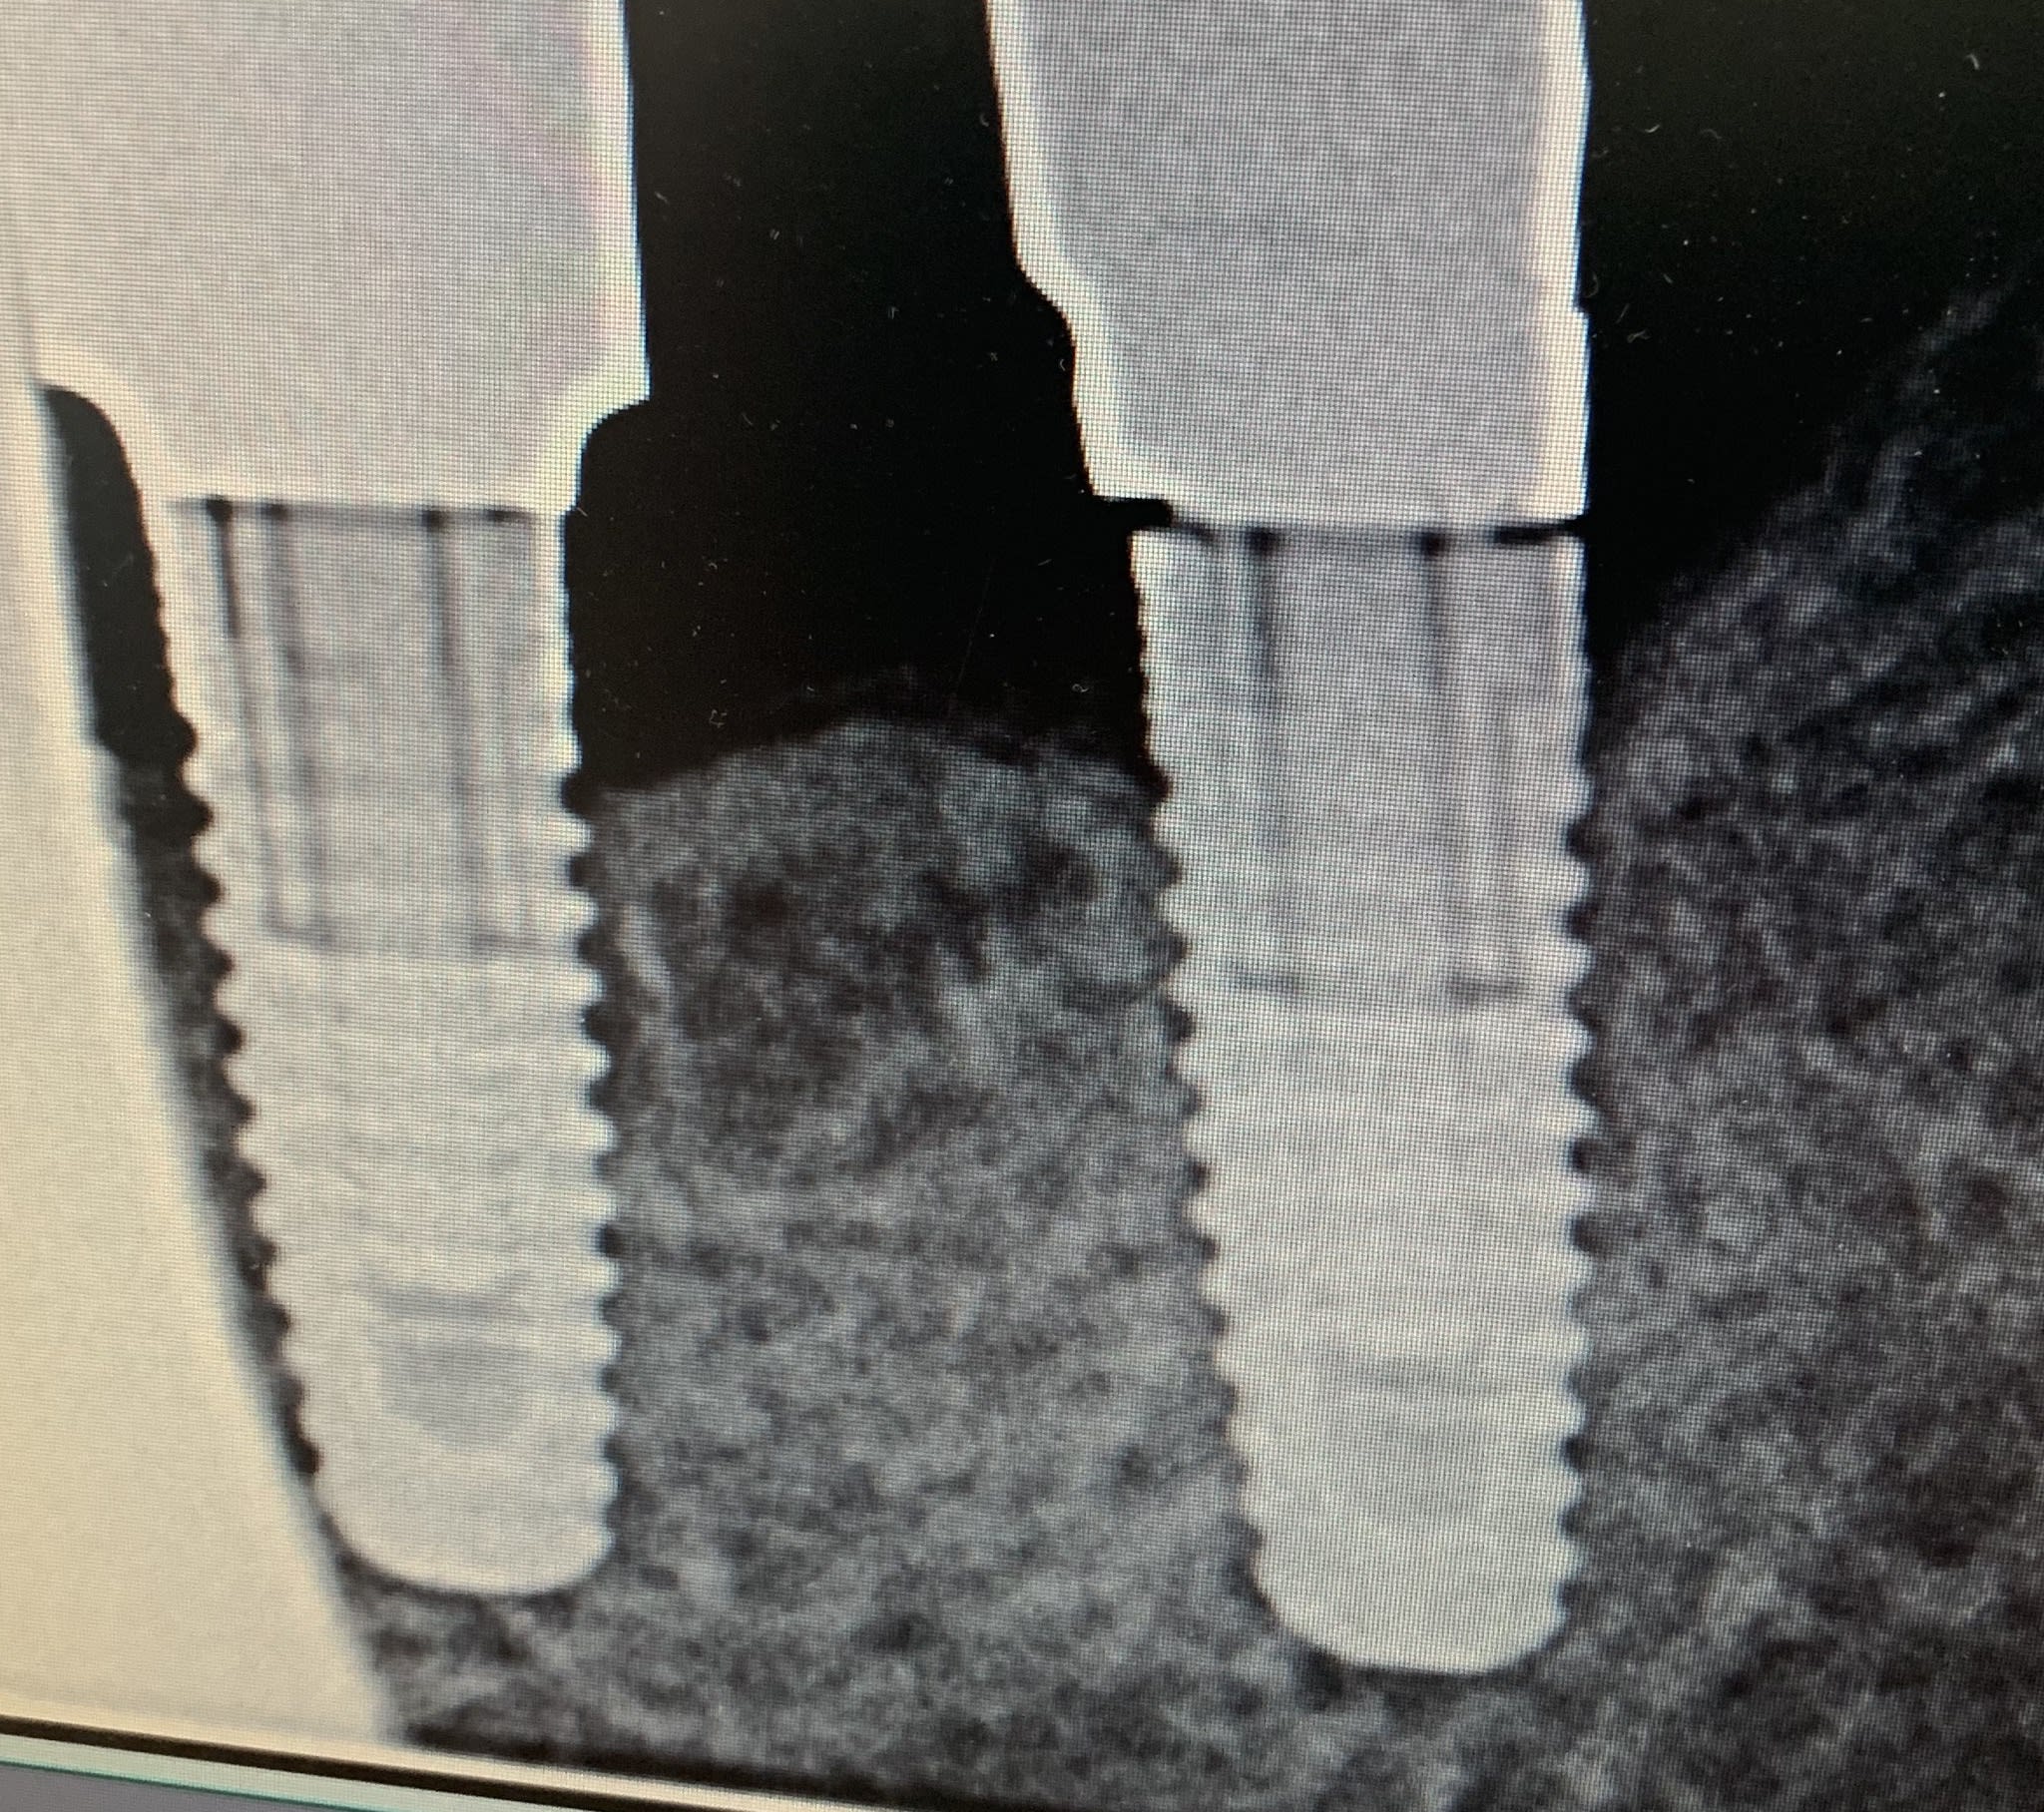

Quelqu’un aurait une idée de la marque de ces implants et modèle ?

Sur whatimplantisthat je pencherais pour un nobel?

je dirais plutôt blue sky bio mais avec trilobe Nobel.....